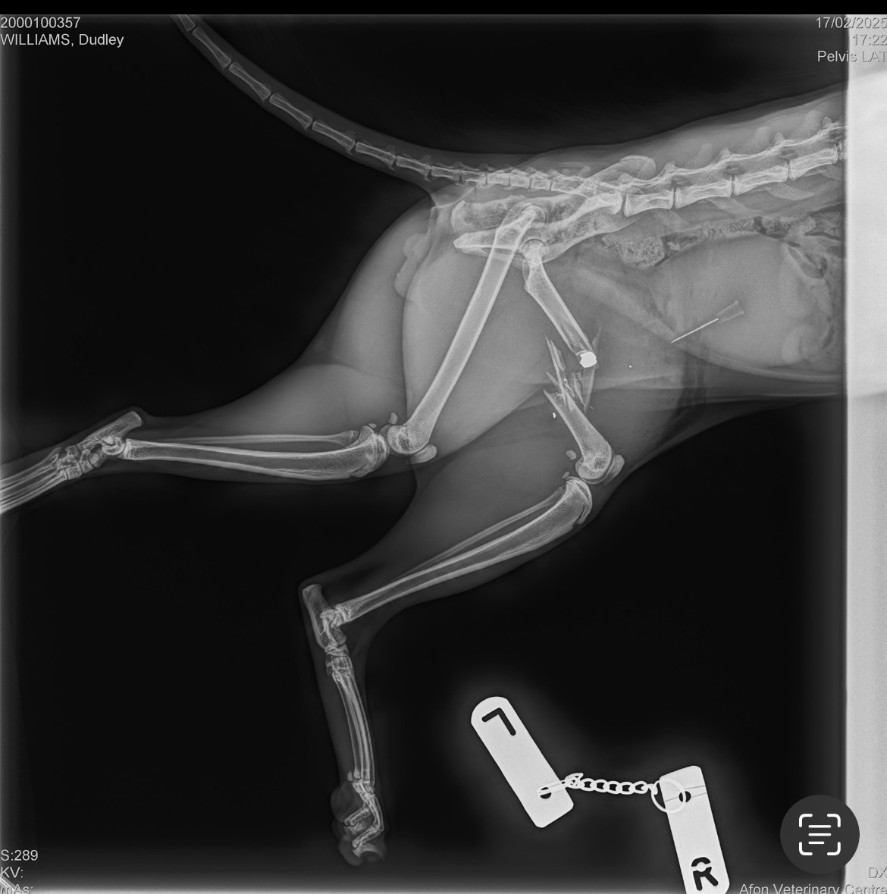

Earlier this year a cat called Dudley was shot by an air gun.

The pellet had shattered his hip and was stuck in between the muscle of his back left leg. As a result he had to have his back left leg amputated.

An appeal was launched to try and find evidence to prove this would have been a deliberate attack.

RSPCA Deputy Chief Inspector (DCI) Gemma Cooper said: “Thankfully he has survived and is recovering from his ordeal – but not without considerable pain and losing a leg.